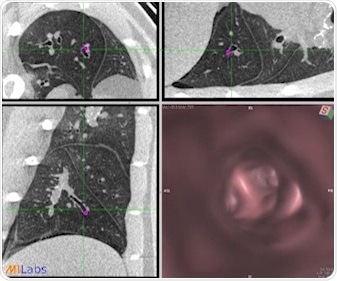

High-resolution detailed ferret CT-lung imaging with virtual endoscopy, see http://www.milabs.com/imaging-solutions/u-ct/ for movie.

The MILabs U-CTUHR system acquired by UAB is designed to meet a broad range of in vivo imaging research applications in variety of animals, ranging from very fast, high-resolution, low-dose bone, tissue and lung imaging, to high-quality dual-gated cardiac and pulmonary analysis. UAB will use the new MILabs U-CTUHR system mainly for evaluation of cystic fibrosis airways disease as well as COPD and pulmonary fibrosis and sinonasal studies.